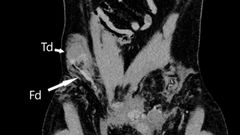

Après avoir réussi à maîtriser l'hémorragie et stabiliser le patient, les médecins se sont penchés sur le cas particulier de la disparition d'un testicule. Des examens médicaux approfondis ont révélé que le testicule droit du patient s'était retrouvé dans son abdomen à la suite de l'impact, où il avait été poussé à travers le canal inguinal, une structure de 4 à 6 cm de long reliant l'abdomen au scrotum. Ce cas extraordinaire a été documenté dans un rapport publié dans le prestigieux BMJ Case Reports.

La luxation testiculaire, bien que rare, est une complication connue chez les hommes ayant des accidents de moto, en particulier chez ceux dans la vingtaine. Cependant, la migration du testicule vers l'abdomen ne survient que dans environ 6 % des cas, ce qui rend ce cas particulièrement exceptionnel.